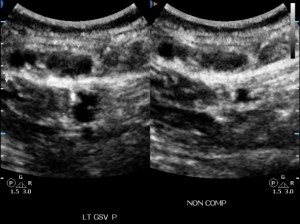

saphenous vein thrombosis ultrasound

GSV thrombus ultrasound (V) with varicosities around it